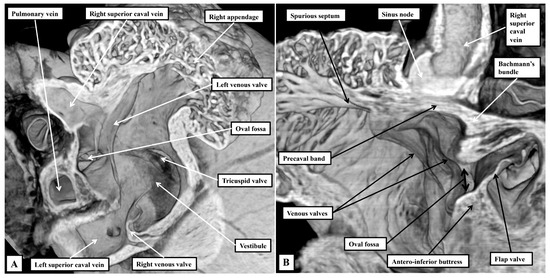

Background: Since the study of Lev and Thaemert in 1973, little has been published concerning the overall arrangement of the murine conduction tissues, in particular with relation to gross anatomical landmarks. We recently emphasised the potential va...